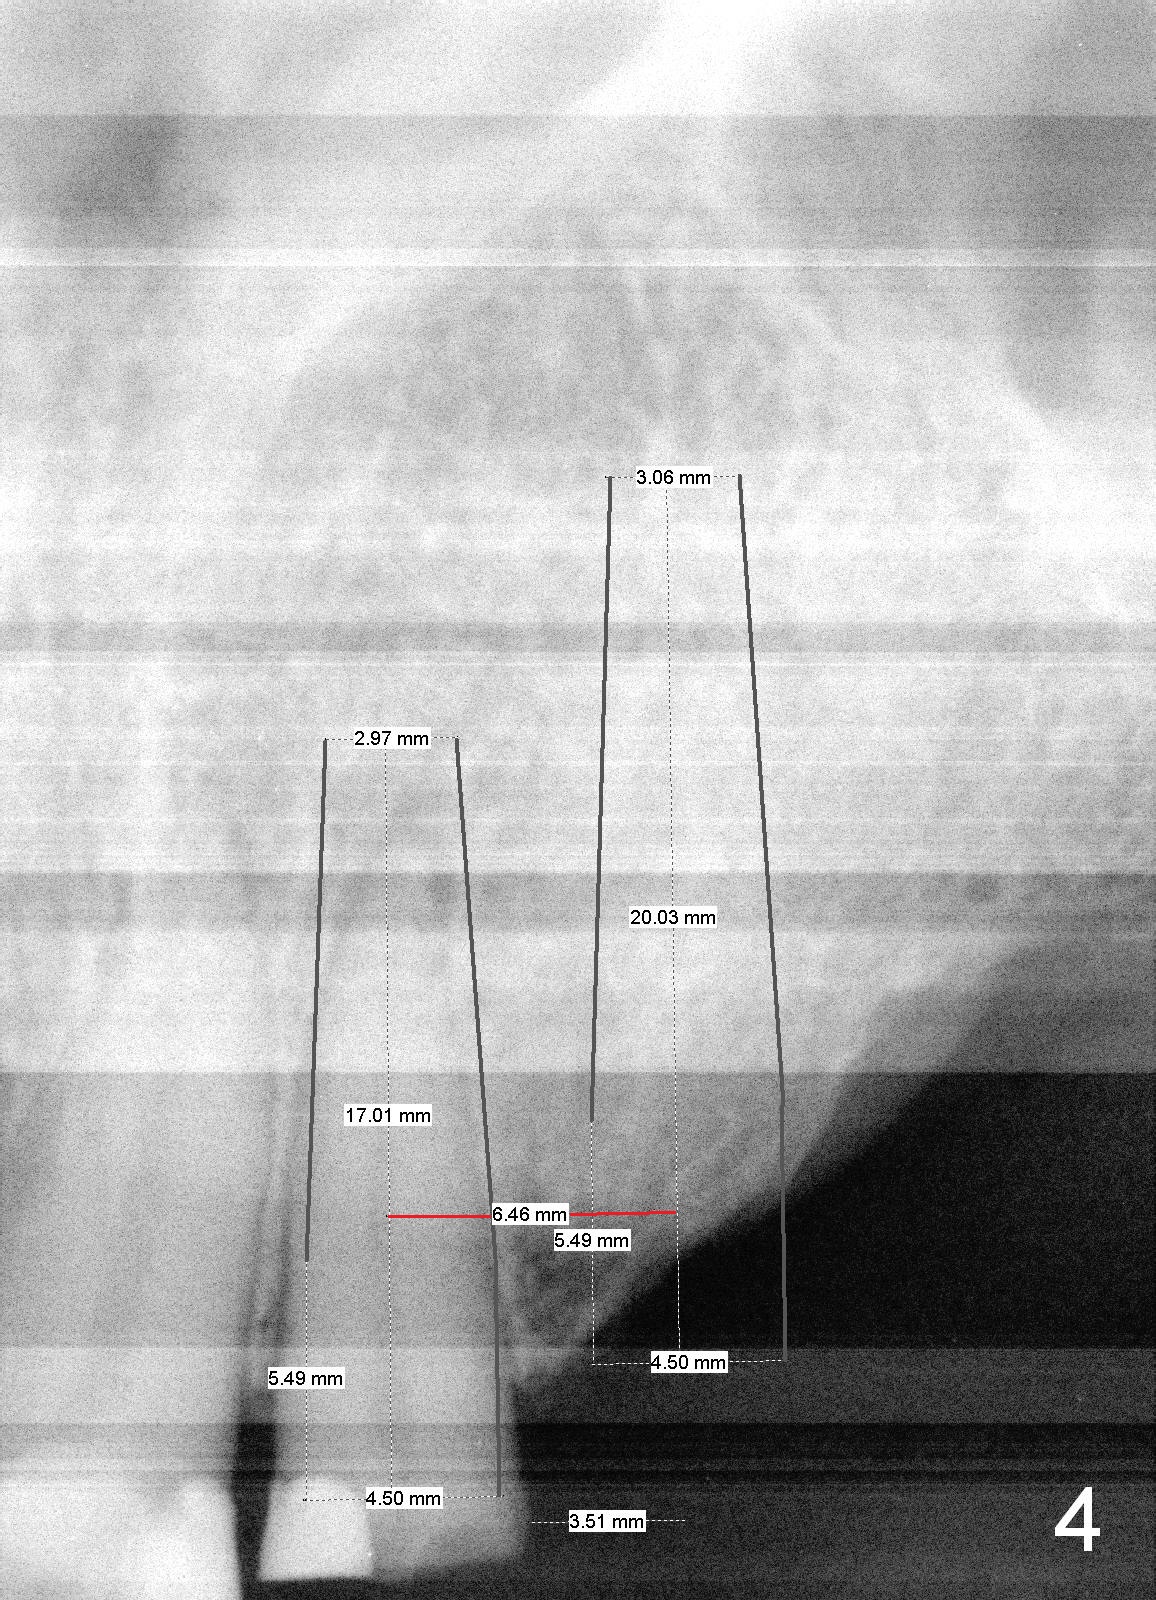

A 70-year-old man (TF) requests implant restoration for the upper left quadrant first (Fig.1), exactly #10 and 11 first (Fig.2-4). There is periapical radiolucency associated with the residual root at #10 (Fig.2 *). Local antibiotic will be Metronidazole. The root of #10 is long and large. The bone at #11 looks loose. Long implants will be placed (Fig.4). Osteotomy preparation should be less.

When initial osteotomy is established at #10 with insertion of a parallel pin, use 4.5 mm implant spacer to determine the initial point for #11 implant site (Fig.4: 6.49 (red line)-2=4.49 mm). 70岁男多个牙齿缺失,5.5年前就诊,同意在10-13位点植牙(图一)。